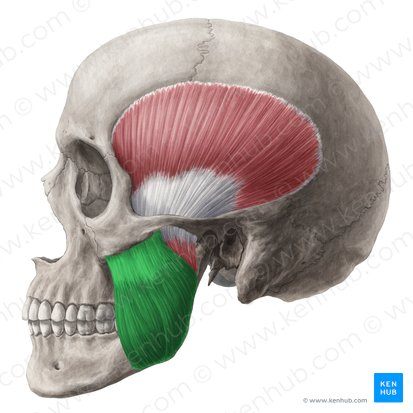

m masseter